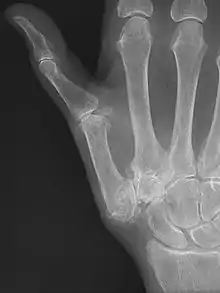

CMC OA can be divided into different stages which show the progression of the disease. The most commonly used classification is the radiological staging protocol according to Eaton and Littler. Four different stages are distinguished on radiological evidence of synovitis, joint space and capsular laxity.[15][21]

Stage 1:

- "synovitis phase"

- slight widening of the joint space

- articular contours are normal

- < 1/3 subluxation of the joint (in any projection)

Stage 2:

- There is a significant capsular laxity

- 1/3 subluxation of the joint

- Osteophytes, < 2 mm in diameter, are present. (usually adjacent to the volar or dorsal facets of the trapezium)

Stage 3:

- > 1/3 subluxation of the joint

- Osteophytes, > 2 mm in diameter, are present (usually adjacent to the volar and dorsal facets of the trapezium)

- Slight joint space narrowing

Stage 4:

- Major subluxation of the joint.

- Very narrow joint space

- Cystic and sclerotic subchondral bone changes are present

- Significant erosion of the scaphotrapezial joint.